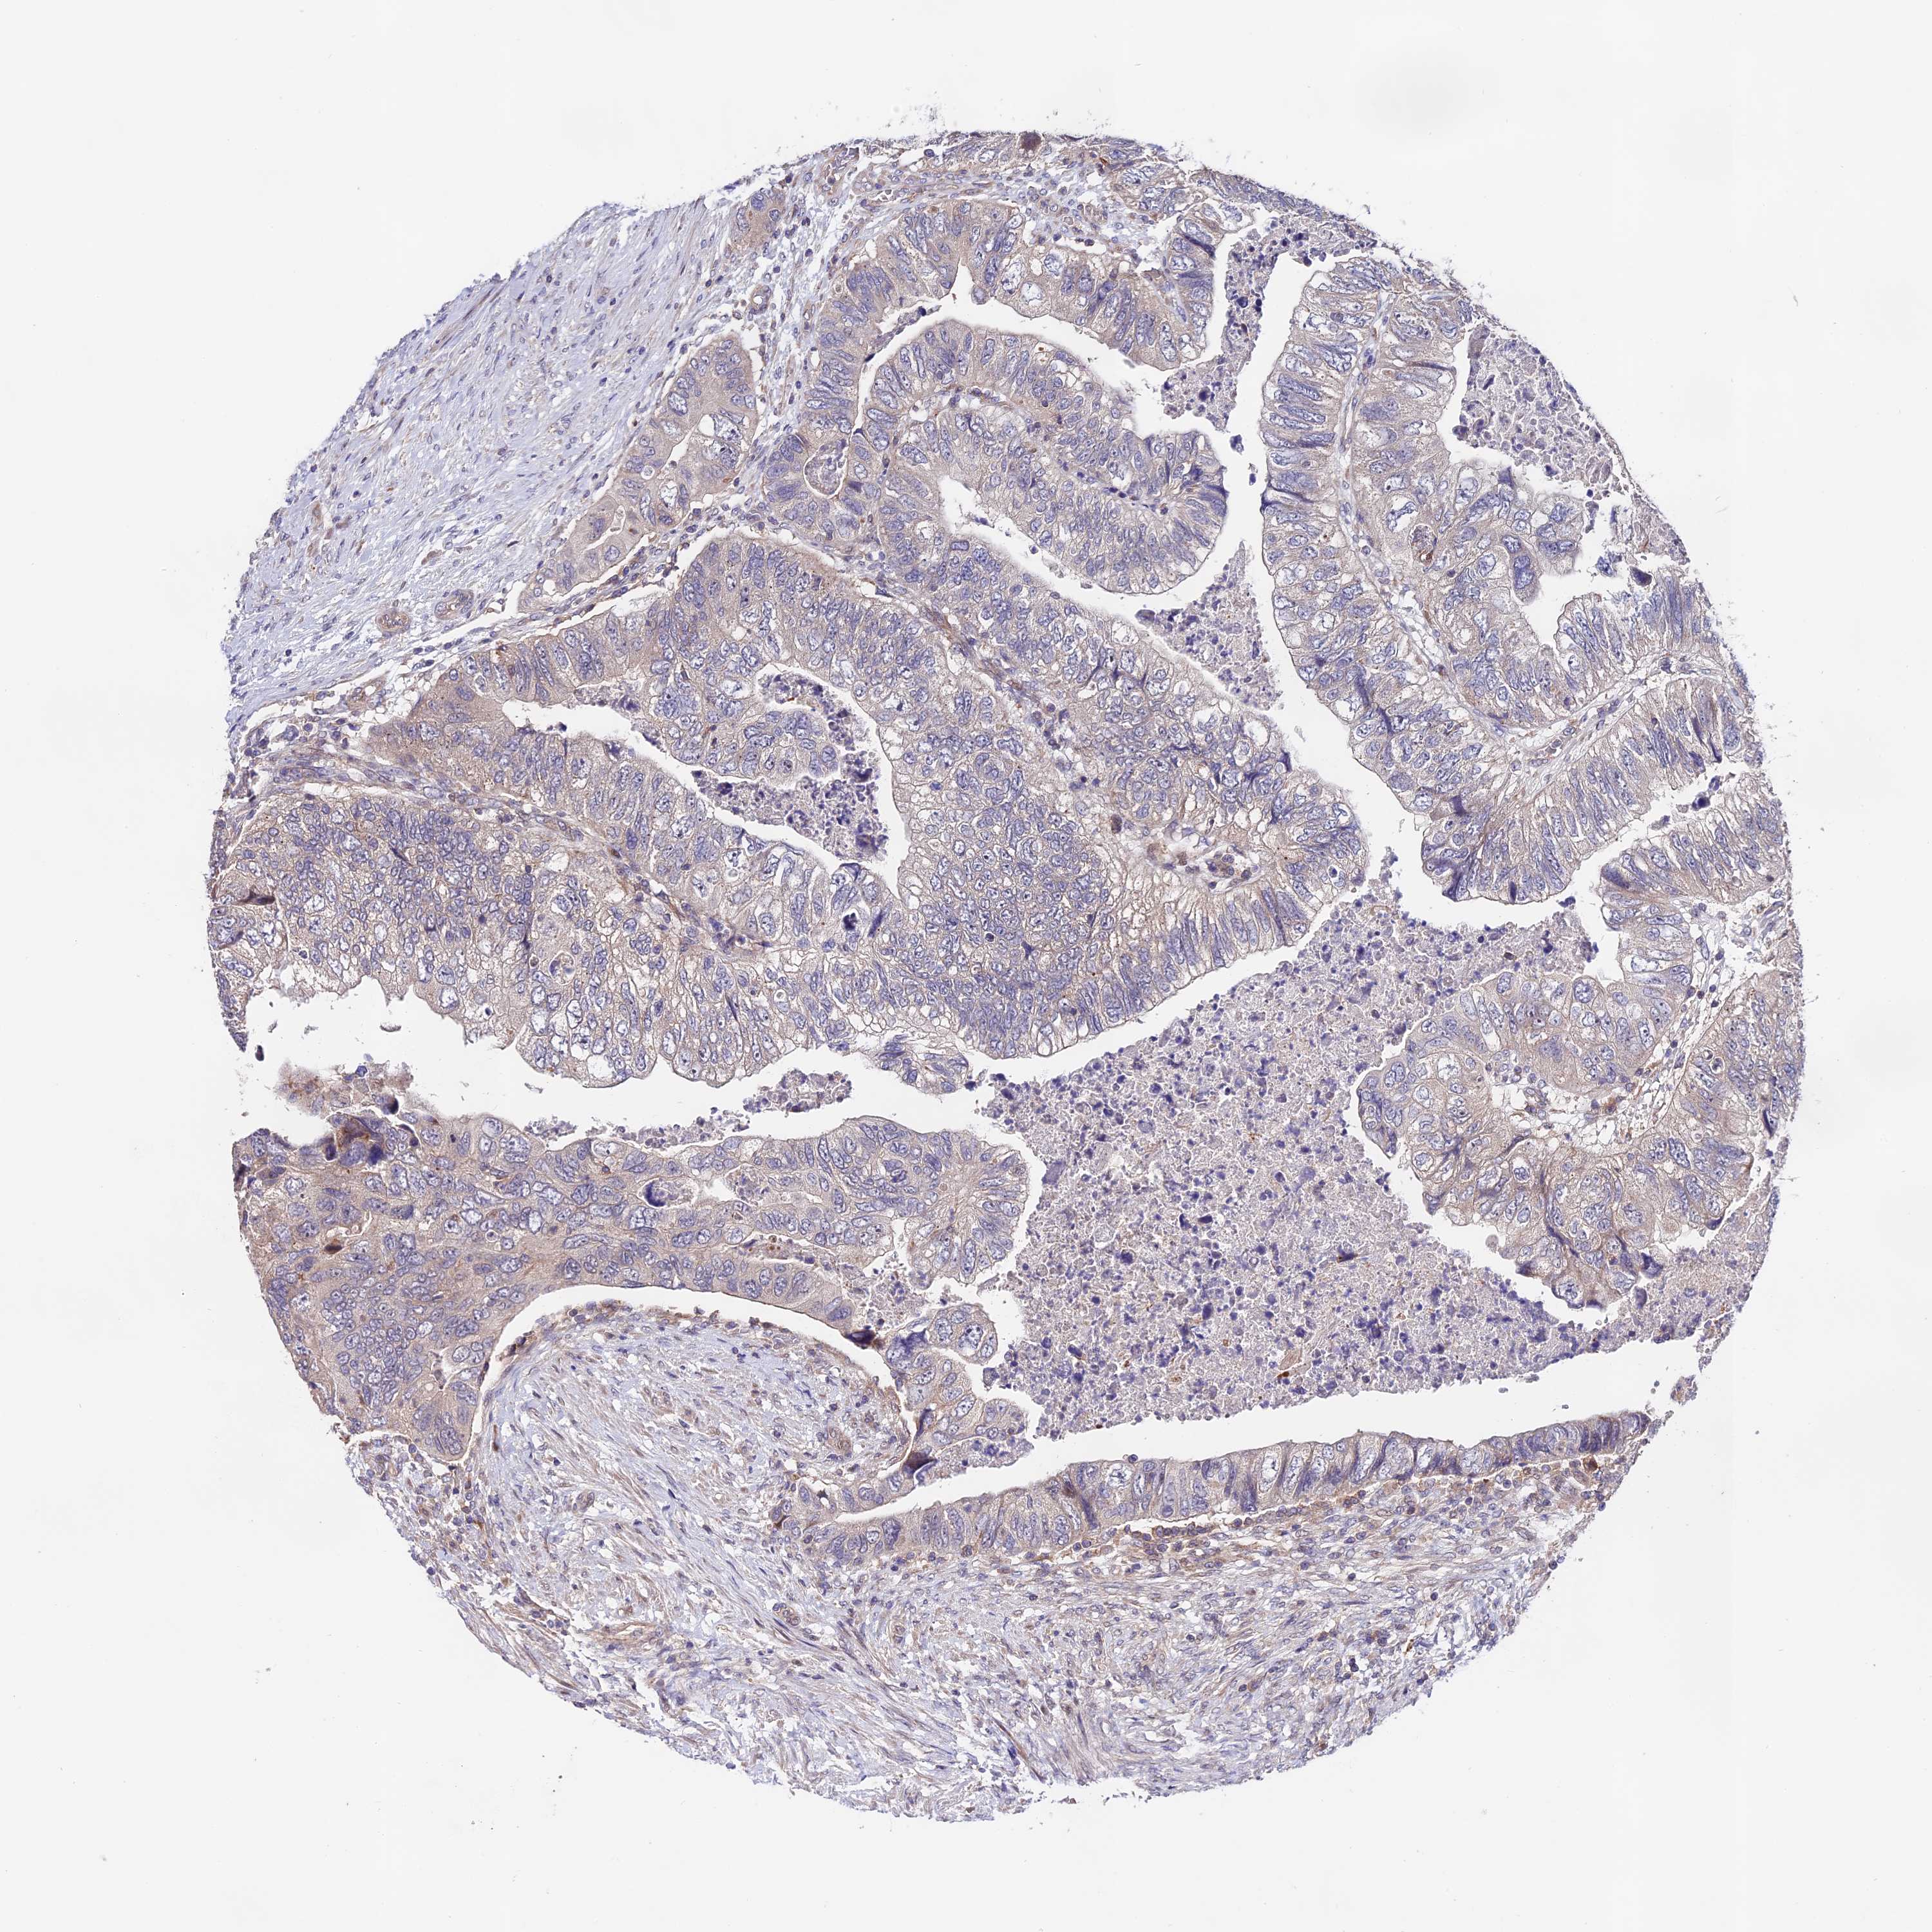

CANCER COLORECTAL CANCER Show tissue menu

Colorectal cancer

Human cancer

Colon adenocarcinoma